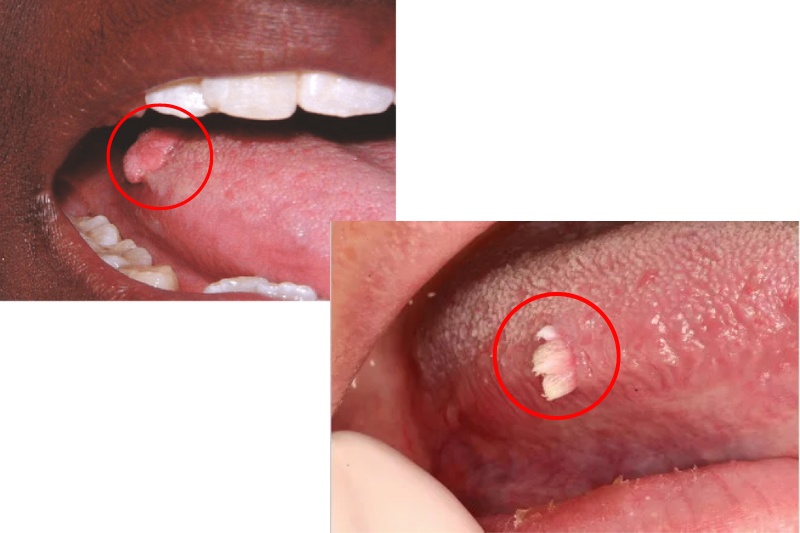

Các triệu chứng nhận biết sùi mào gà ở lưỡi

Điều cần lưu ý là bệnh sùi mào gà ở lưỡi dễ bị nhầm lẫn với nhiệt miệng, vì cùng có thể là nổi mụn thịt đỏ ở lưỡi. Do đó có nhiều người bệnh thường chủ quan và bỏ qua các dấu hiệu sớm của bệnh để đi khám kịp thời.

Các triệu chứng nhận biết sùi mào gà ở lưỡi, bao gồm:

- Trên bề mặt cuống lưỡi, thân dưới lưỡi xuất hiện các u nhú, mụn cóc nhỏ màu hồng, đường kính khoảng 1 đến 20 mm;

Biểu hiện của bệnh u nhú tiền đình papillomatosis

- Lưỡi nổi mụn thịt màu đỏ với các vị trí đối xứng nhau hoặc mọc thành dải trên bề mặt của hai bên lưỡi.

- Mụn thịt màu đỏ, hồng có chân và cuống riêng, khác với mụn cóc sùi mào gà chỉ có 1 chân hoặc cuống nhưng phát triển thành từng mảng như mào gà.

- Mụn thịt ở lưỡi không bị vỡ mà tự teo dần rồi mất đi.